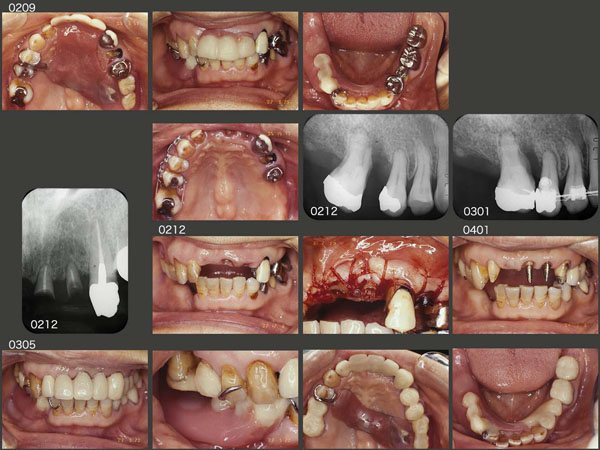

まず,人工歯を旧義歯に付与することで,上顎前歯の審美回復を図った.つぎに,右上6を近心に移動した.移動にかかった期間は約1ヵ月と早いが,その位支持歯槽骨がない状態であった.さらに,左上1,2および4の歯冠長を延長し,歯肉縁上歯質の確保を行った.2003年5月,基礎治療が終了し,ここから最終補綴装置の製作にとりかかった.

初診終了後約7年間は特に問題なく経過した.しかし,2011年2月に,まず左下4のメタルボンド冠の陶材が少し破損した.しかし,特に支障がないのでこのまま経過をみることにした.右下は犬歯以降が失われているため,どうしても咬合・咀嚼の中心は左側の咬合支持歯にならざるを得ない.したがって,左下4の存在するエリアに常に咬合力が加わるため,トラブルが生じやすい.

この状況を少しでも緩和する目的すなわち右側の義歯側でもっと咬んでもらうために,人工歯の排列位置を変更した.これまでは,上顎の天然歯としっかり咬合させて排列したため,人工歯の位置が頰側に外れていた.そこでまず顎堤上に排列したが,如何せん上顎天然歯との咬合接触面積が少なくなってしまったため,若干頰側に戻した位置を最終的な下顎の人工歯の排列位置とした.

人工歯の位置を変更したことが災いしたためか,11年10月,右上6の歯の動揺が大きくなり,このままでは連結固定してある右上5に悪影響を及ぼすため,抜歯した.装着されていた金属の冠をそのまま人工歯として再利用した.